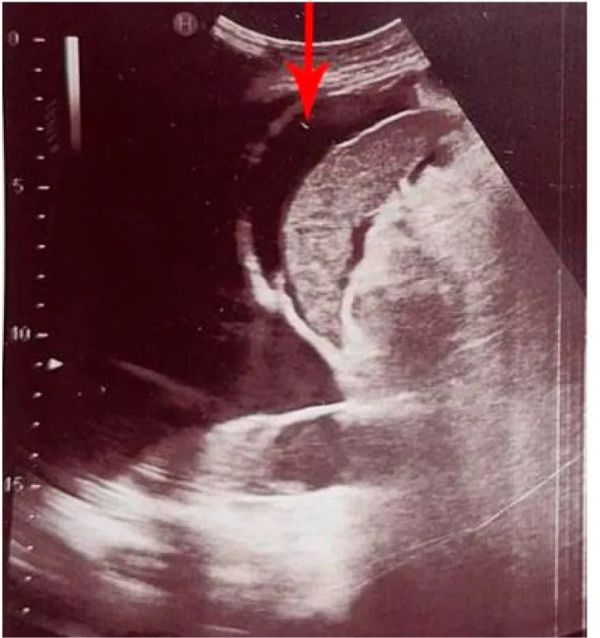

腹腔内游离液(IPF)是腹膜腔内液体的病理性积聚,是各种疾病的症状[22]。急诊患者IPF最常见的病因是创伤性出血、腹水、胆汁、尿漏和异位妊娠破裂[23]。用于检测和量化游离液体量的初始诊断程序是腹部超声(US),这也有助于确定IPF积累的原因。此外,腹部美国可以在穿刺术期间提供指导,以准确确定IPF的定位,同时确保脾脏和其他重要结构在手术过程中不受伤[24,25]。美国在检测IPF方面的敏感性和特异性超过90%,而POCUS在有经验的手中可检测到高达10 mL的游离腹腔积液[26,27]。在腹部,IPF最常局限于肝周(在莫里森袋中)或脾周(图 1),而在骨盆中,它最常局限于道格拉斯袋[28]。

图 1脾脏腹膜内游离液 (IPF)(红色箭头)。